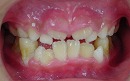

今回は、歯並びが悪く、顎が小さいお子様の症例です。

矯正前 矯正後

今回も治療には、独自の方法とビムラー装置等を利用しました。

咬合バランスをよくする為には、

顎を大きくするだけでは不十分と考えています。

その為、かみ合わせの高さなどを立体的に改善していく事を心がけて治療しています。